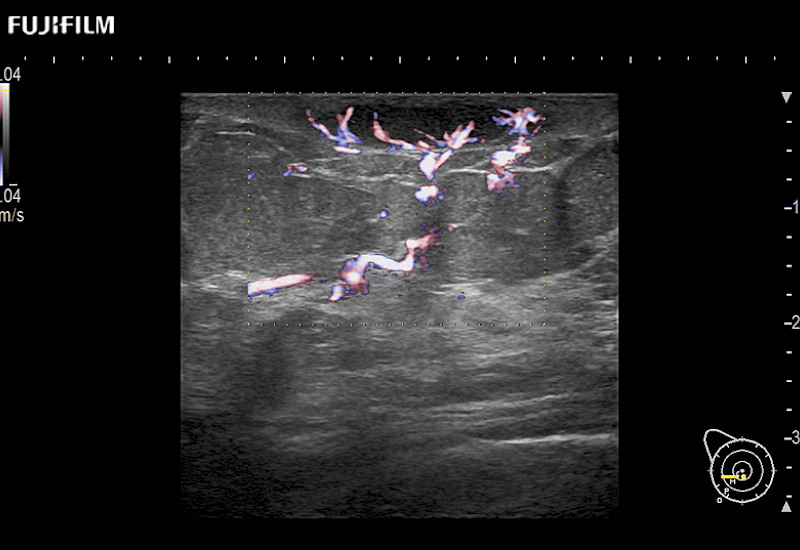

Learn moreFujifilm Healthcare continues to listen to the experts, our neurosurgeons, by developing an ultrasound system specifically designed for the Operating Room.

Guidance is the fundamental purpose for all of our surgical ultrasound technology. Fujifilm Healthcare is committed to designing tools that help neurosurgeons navigate inside the human body and provide the necessary information to immediately make critical surgical decisions.

With the ARIETTA Precision the next level of surgical ultrasound is here.